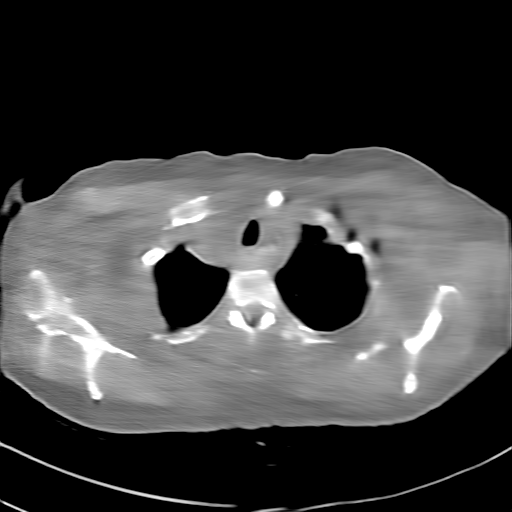

GT

FBP

HQS-CG

DuDoNet

Meta

Meta_re

EPNet

Qualitative Results Comparison. We also visualize the reconstruction results of these methods on AAPM-test and COVID-test datasets. As in the first three rows of Fig. 4, the reconstructed images from ours and retrained MetaInvNet show the best visualization quality on AAPM-test set across different angle numbers. Besides, our results show sharper details with the additional utilization of in the projection domain. When testing the reconstructed image on the COVID-test set, our result also gives sharper details but with more artifacts since the data distribution is very different. Although HQS-CG has achieved better quantitative results on the COVID-test dataset, the reconstructed image of their model in the fourth row is even smoother than FBP.